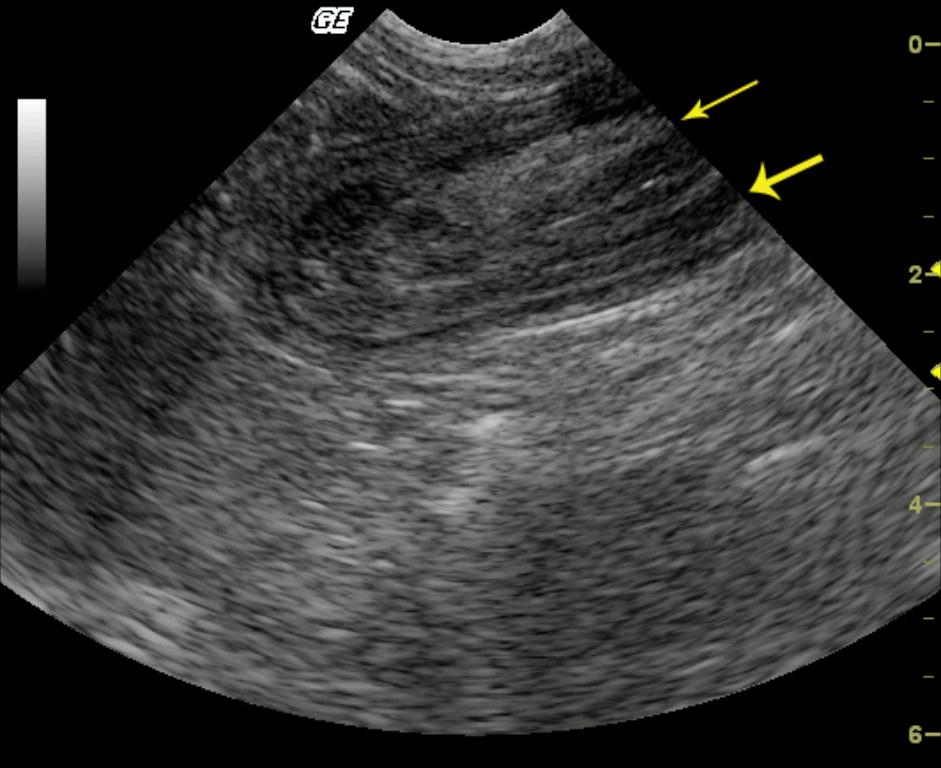

This 2-year-old FS DSH was presented for progressive anorexia and lethargy over the previous week. Physical exam revealed a palpable mid caudal abdominal mass and moderate dehydration. CBC and blood chemistry were normal. Radiographs confirmed a soft-tissue density in the mid caudal abdomen.